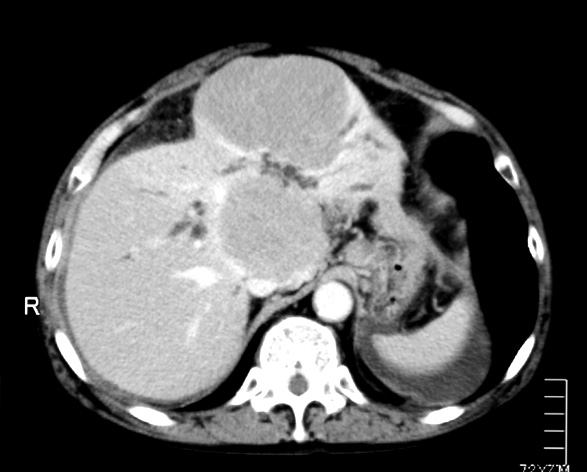

72歳 男性

腹部膨満感で他院を受診. 黄疸と心窩部腫瘤を触れCTでは管内胆管の拡張と左葉の腫瘤を認めた。精査治療のため当院消化器内科を紹介される。 ENBD留置などの処置で減黄を行う。ERCPによる胆汁細胞診では少数のatypical lymphcytesを認めるが確診できず。肝生検をおこなった。

既往歴:1年前肝右葉の肝膿瘍。ドレナージで治癒。組織の採取は行っていない。